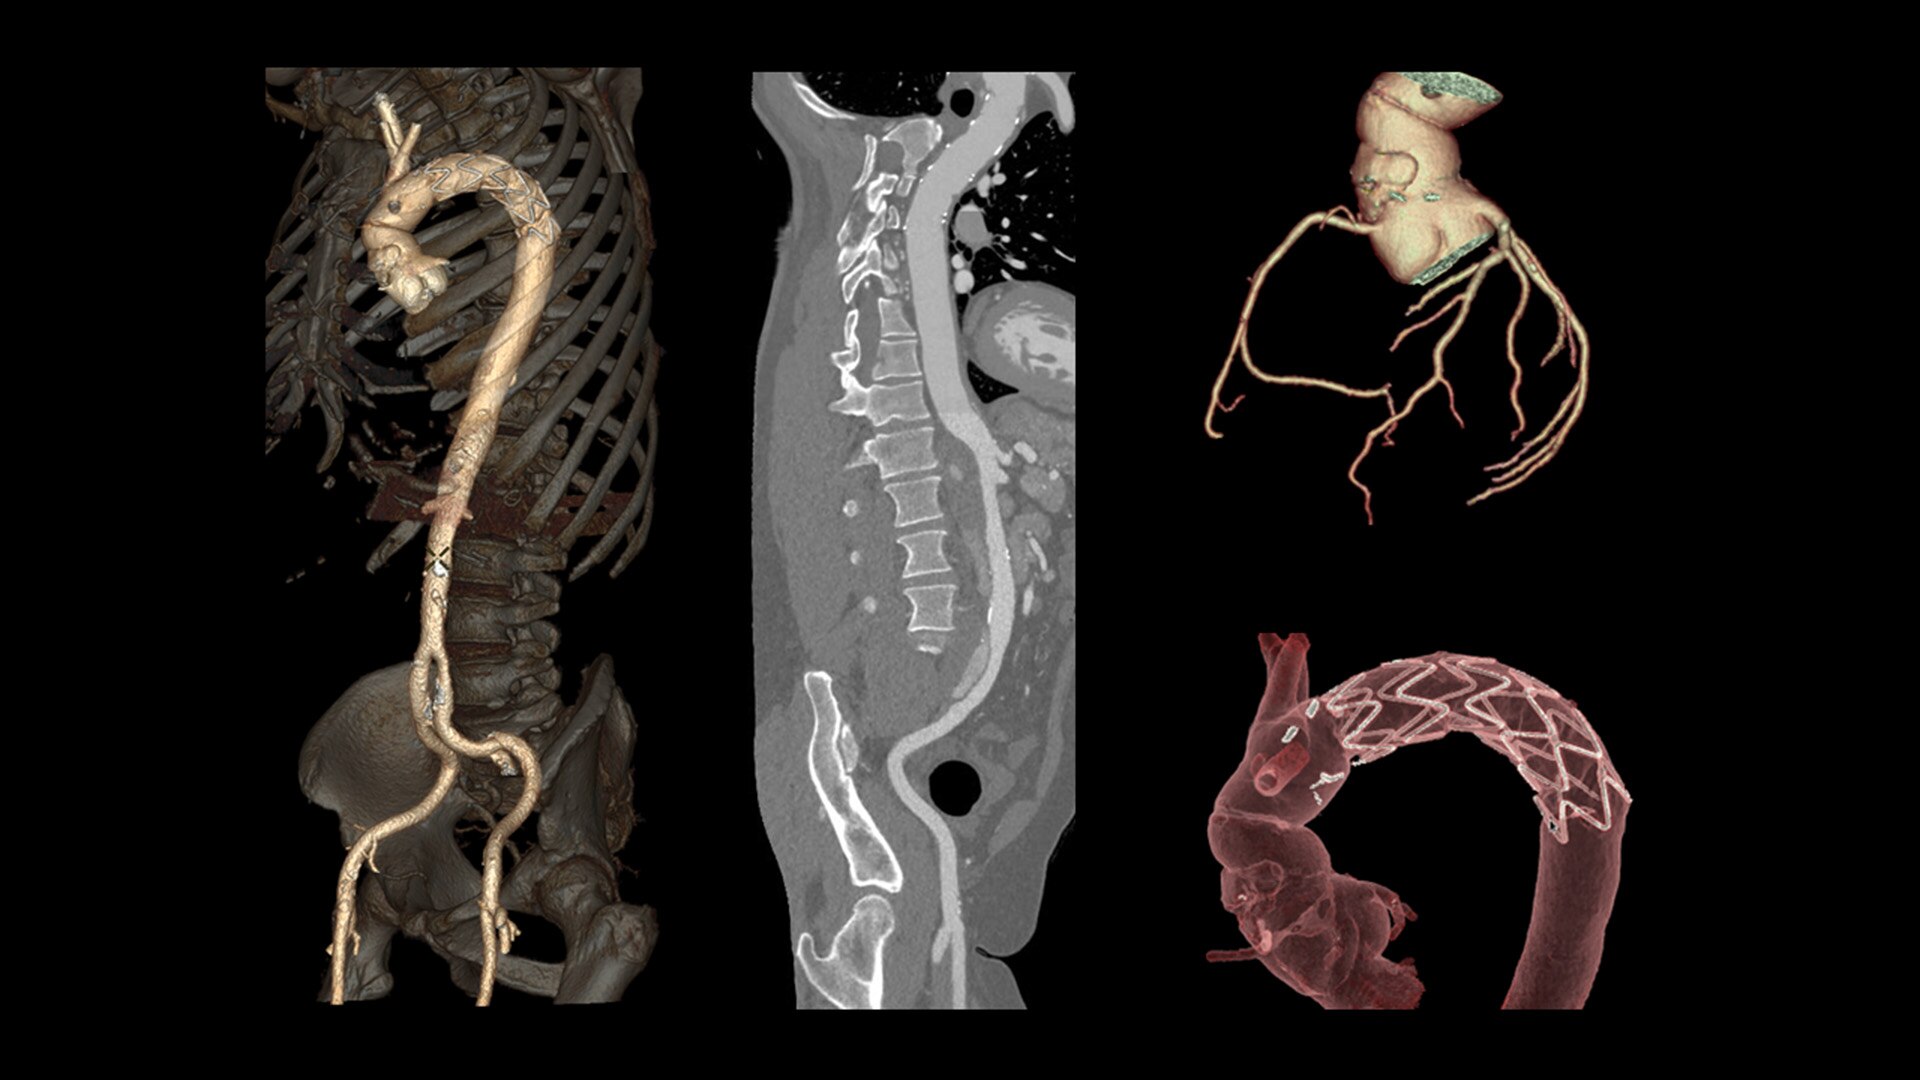

Cardiac CT has become a front-line, non-invasive imaging tool for diagnosing, treatment planning and monitoring of cardiovascular disease

Healthcare providers are striving to improve patient health but are struggling with increasingly complex exams, insufficient or inexperienced staff, and operational and capital efficiency. Revolution™ Vibe, designed to deliver leading-edge technology, features advanced cardiovascular capability. It improves patient access and operational efficiency, prioritizes patient care and supports your facility's growth with lower lifecycle costs.

Consistent, exceptional image quality for every patient

Unlimited 1-Beat Cardiac is designed to provide consistent, high-quality imaging for accurate diagnoses, even in challenging patients with atrial fibrillation, breath-holding difficulties, heavily calcified coronaries, in-stent restenosis, and situations where an ECG trace is unavailable.